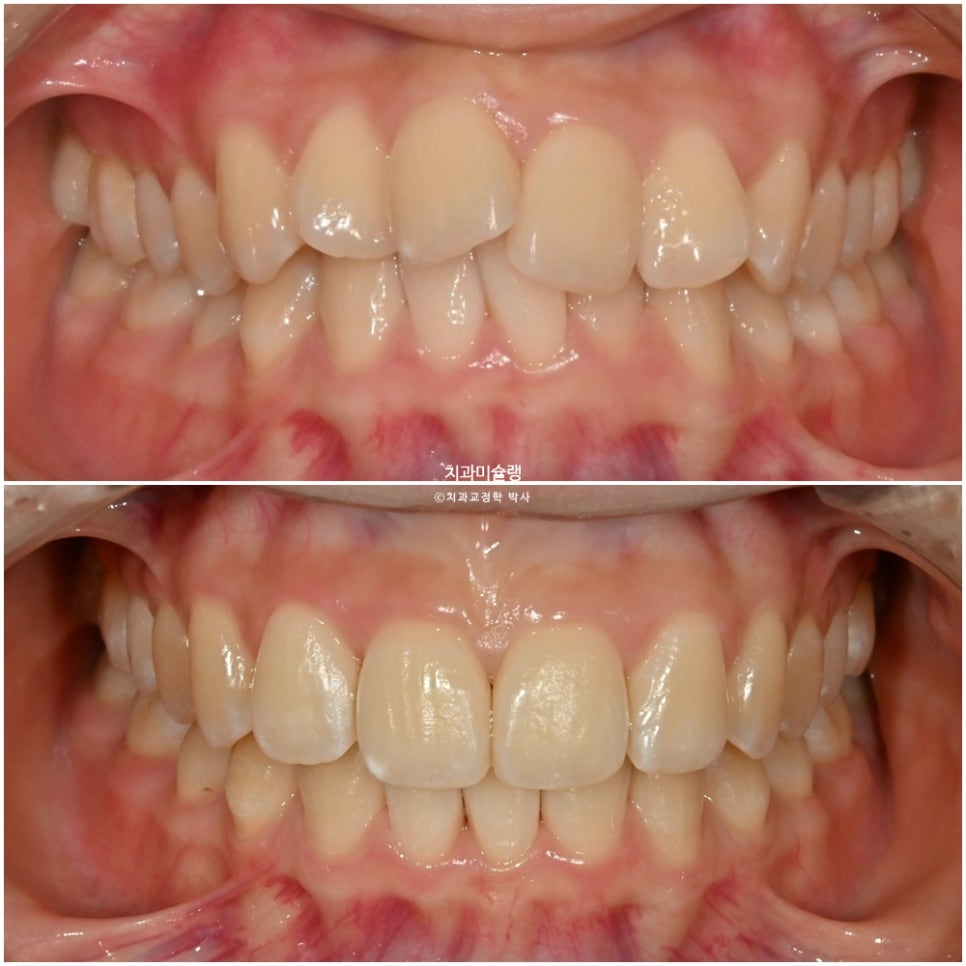

이제 전후비교 볼게요.

2025.03-2026.03

깔끔해진 미소와 잘 유지된 입동굴

45도 측모 에서는 웃을때 약간의 돌출감은 여전히 남았으나 환자분은 만족하셨죠.

교정 전후 입매 변화는 없습니다.